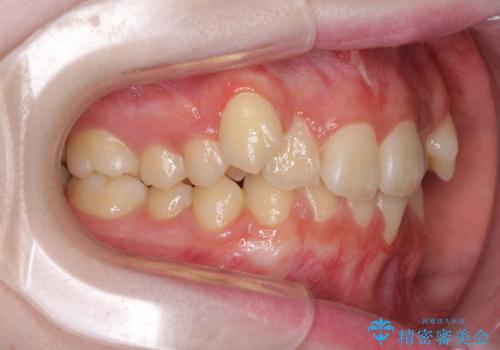

- 上下前歯のデコボコを気にして来院された患者様です。

前歯の叢生は強かったのですが、口元が引っ込んでいる印象であったため、非抜歯にて矯正治療を行うこととしました。

インビザラインでの自己管理は難しいとのことで、ワイヤー装置にて矯正を行うこととしました。